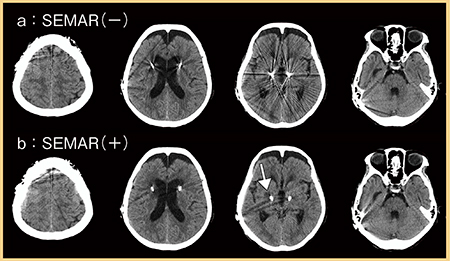

■DBS術後評価にSEMARは有用か4)

SEMARは,Single Energyデータに対し,Forward projectionとBack projectionを複数回繰り返して金属アーチファクトを選択的に低減する手法である。

近年,パーキンソン病などの患者に多く行われているDBSでは,CT撮影を行うと強いアーチファクトが出現することが多い。そこで,DBS術後評価におけるSEMARの有用性を検討した。

症例5は,パーキンソン病の70歳代,女性に対し,両側視床下核にDBSを施行した症例である。SEMARの適用ありとなしの画像(図5)を比較すると,SEMAR適用ありではリード線近傍のアーチファクトが著明に低減している(b)。これにより,深部灰白質の陳旧性の血管障害と思われる低吸収域が明瞭となった(図5 b ↓)。SEMAR適用ありの方が頭頂側のアーチファクトがやや目立つが,これは脳表のリード線の影響であると考えられる。

定性評価を行ったところ,金属アーチファクトはSEMARを適用することで有意に減少し,脳の構造の描出能も有意に向上するという結果であった。

以上より,SEMARの適用によってDBS装置からの金属アーチファクトが低減され,脳実質の評価に有用である。

図5 症例5:SEMARの適用ありとなしの画像比較

(参考文献4)より引用転載)